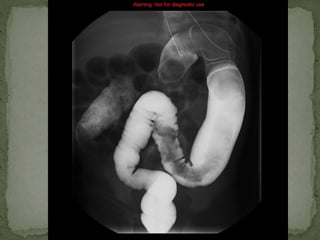

 Barium enema single contrast study- 18th June, 2013

 Moderate distension of large bowel without definite

haustral pattern

 May represent distal segment Hirschsprung disease

 Findings can also be seen in constipation and myxdema

 Barium enemasingle contrast study- 18th June, 2013  Moderate distension of large bowel without definite haustral pattern  May represent distal segment Hirschsprung disease  Findings can also be seen in constipation and myxdema